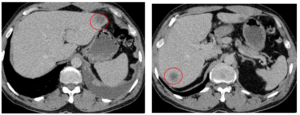

Điều trị bệnh nhân ung thư đại tràng Sigma di căn gan tại Trung tâm Y học hạt nhân và Ung bướu, Bệnh viện Bạch Mai

Điều trị bệnh nhân ung thư đại tràng Sigma di căn gan tại Trung tâm Y học hạt nhân và Ung bướu, Bệnh viện Bạch Mai GS.TS. Mai Trọng Khoa, BSCK II Nguyễn Đức Luân, PGS.TS. Phạm Cẩm Phương Trung tâm Y học hạt nhân và Ung bướu, Bệnh viện...